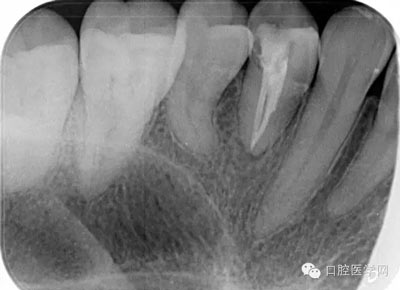

第七步:根管充填 使用對應(yīng)錐度及號數(shù)的牙膠尖充填。